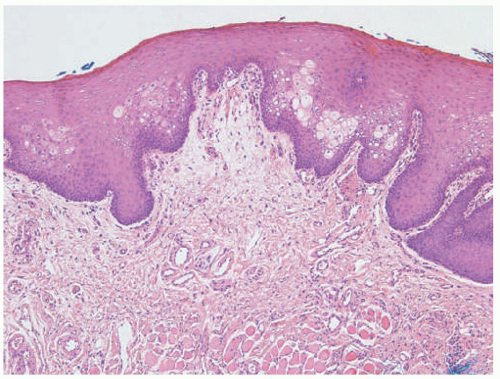

plaques that primarily involves skin folds. The posterior and lateral folds of the neck are commonly affected. Early acanthosis nigricans may be heralded by slight hyperpigmentation that later eventuates into thickening of the skin. Other affected areas include the dorsal knuckles, genitalia, perineum, face, thighs, breast, and axillae. Generalized acanthosis nigricans may occur, which can present with involvement of the oral mucosa, lips, and eyelids and may herald an underlying malignancy.33 Similarly, the finding of “tripe palms,” or velvety thickening of the palms and dorsal hand, may also be paraneoplastic.34 Rarely, acanthosis nigricans may present in the form of an epidermal nevus, which may be heritable in autosomal dominant fashion and can present at birth, childhood, or puberty.35